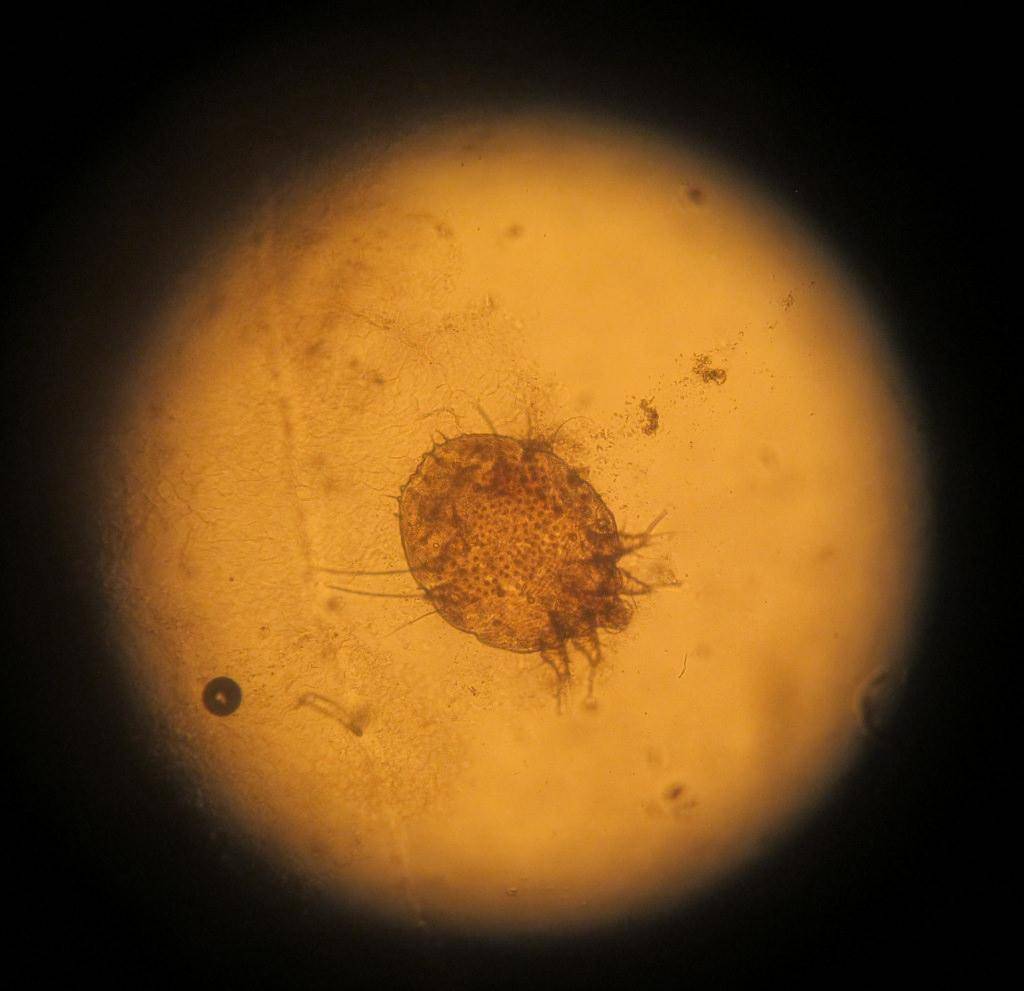

Фото клеща-возбудителя саркоптоза у свиней Возбудитель S. suis — мелкий, незаметный простым глазом клещ, овальной формы, сплющенный в дорзо –вентральном направлении, длиной 0,25-0,50 мм.

На спинной поверхности клеща имеются чешуйки и наклоненные назад щетинки. Ноги у клеща короткие, толстые. Самцы меньше самок. У самок на первой и второй, а у самцов также и на четвертой паре ножек имеются воронкообразные присоски на длинных отростках.

Конечности, не имеющие присосок, заканчиваются длинной щетинкой. Спереди тела клеща расположен короткий хоботок. Ротовые органы грызущего типа. Трахеи, кровеносная система, глаза- отсутствуют.